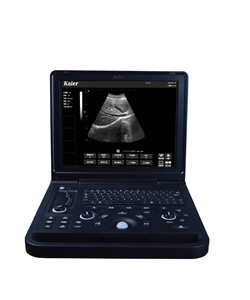

兽用B超机

兽用B超,动物B超机生产厂家.适合牛羊猪猫狗等动物,牲畜,宠物B超仪器,凯尔兽用B超。

兽用B超,动物B超机生产厂家.适合牛羊猪猫狗等动物,牲畜,宠物B超仪器,凯尔兽用B超。